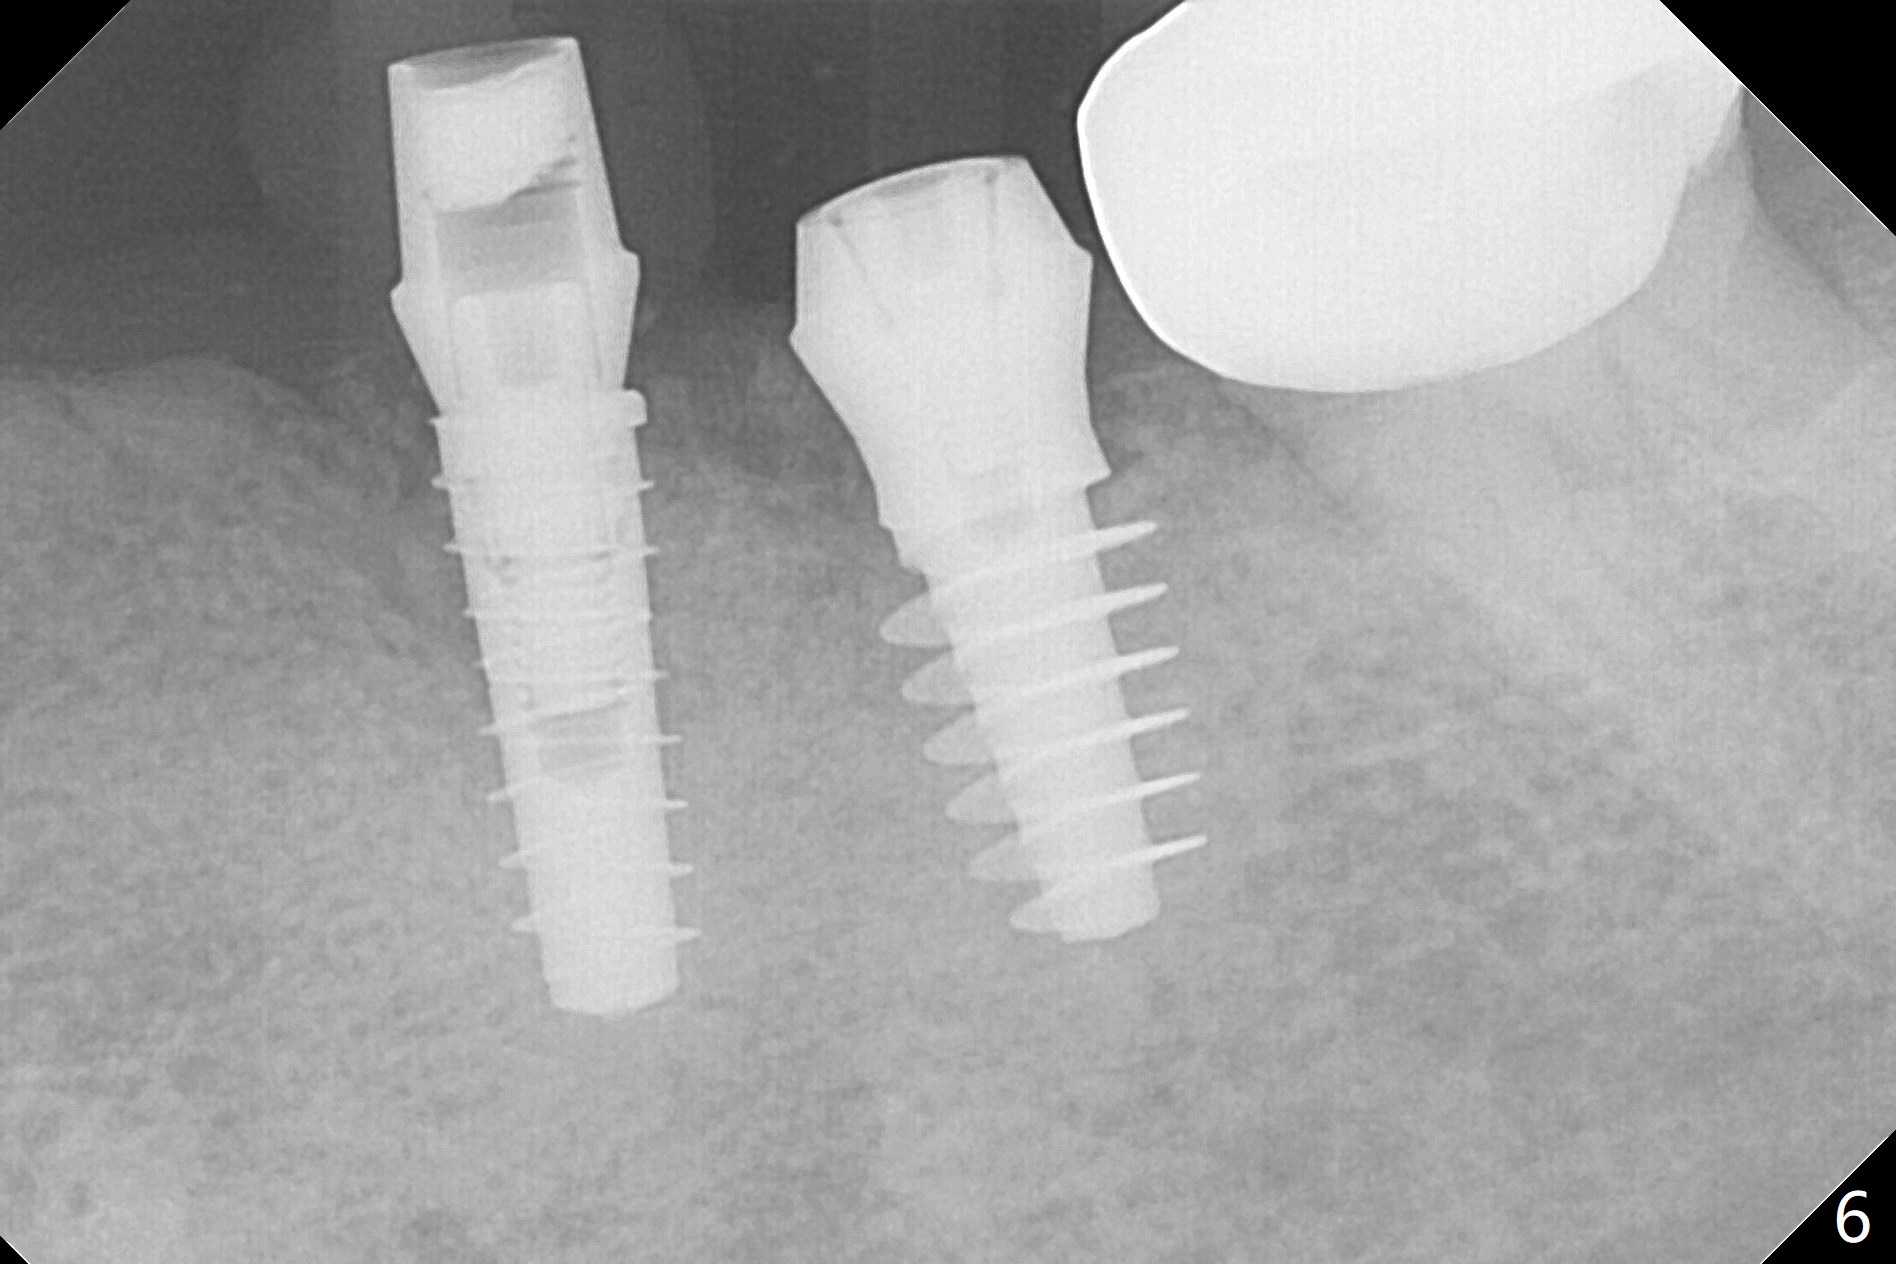

In fact the ridge at #19 is wide (Fig.1); there is enough bone to place a 5 mm implant (Fig.2 (5 mm implant positioner)). The gingiva is 3 mm in thickness. After use of Marking Drill, 5.3 mm Magic Drill (MD) for 9 mm and 4.8 mm MD for ~10 mm, a 5.5x9(3) mm Magicore is placed with primary stability, but too deep. When the implant is reversed, stability loses. After the autogenous bone from bone core is placed in the osteotomy, stability restores to a certain degree (Fig.3); there is no occlusal clearance when a 4.3x3 mm solid abutment is placed. Vera graft is placed around the implant (Fig.4 *) and a healing screw is placed (Fig.4,5).

There is no bone loss at #20 or 19 six and 3 months postop, respectively (Fig.6,7). After placing and trimming a 4.3x3 mm Magicore solid abutment, impression is taken (Fig.8). After cementation for #19 and 20 crowns, the crown of #20 is removed for cement removal; attention is paid to cement removal around the crown at #19. In fact, the removal is ineffective with the crown of #20 is reseated and retightened (Fig.9 >). Repeated removal proves to be futile (Fig.10 >). The most effective method will be to take X-ray immediately after #20 crown removal and reseating without torque so that it will be easier to remove the remaining cement if needed. It may be ok in term of hygiene, since proximal brush is used daily. While the crowns at #18 and 19 are being redone because of food impaction, the tooth #18 needs RCT; the Magicore seems to have no bone loss 4 months post cementation (Fig.11). CBCT shows that the Magicore seems to have been placed in the middle of the crest 7 months post cementation (Fig.12 (B: buccal)). The gingiva at #19 is apparently healthy 8 months post cementation. The crown at #19 is recemented 10.5 months post cementation (Fig.13).